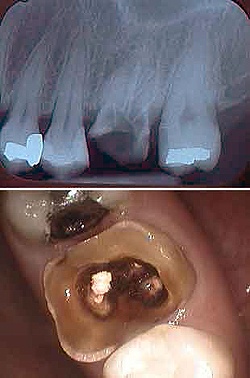

Перелом зуба. Травматическое повреждение зуба, сопровождающееся нарушением целостности его корня или коронки. Встречаются различные виды перелома зуба: перелом эмали, дентина и корня зуба. Проявляются резкой подвижностью и смещением травмированного зуба, интенсивной болью. При переломах коронки зуб удается сохранить с последующим косметическим восстановлением, при переломе корня - требуется его удаление. При травме корня высок риск развития периостита, остеомиелита и тд осложнений.

Болезненные ощущения при механическом и термическом раздражении зависят от типа и локализации перелома, а так же от подвижности зуба. Во время осмотра обнаруживается отек мягких тканей приротовой полости и точечные кровоизлияния в кожу и слизистую. Перелом коронки зуба клинически проявляется в виде ее дефекта, часто такой перелом сопровождается вскрытием пульповой камеры. При переломе корня зуба, зуб становится подвижным, его перкуссия резко болезненна, а коронка иногда приобретает розовый оттенок.

Перелом зуба может быть незначительным в виде откола эмали зуба, либо значительными когда отмечается перелом дентина с обнажением или без обнажения пульпы и перелом корня зуба. Полными называются переломы со вскрытием пульпы, неполными - без вскрытия пульпы.